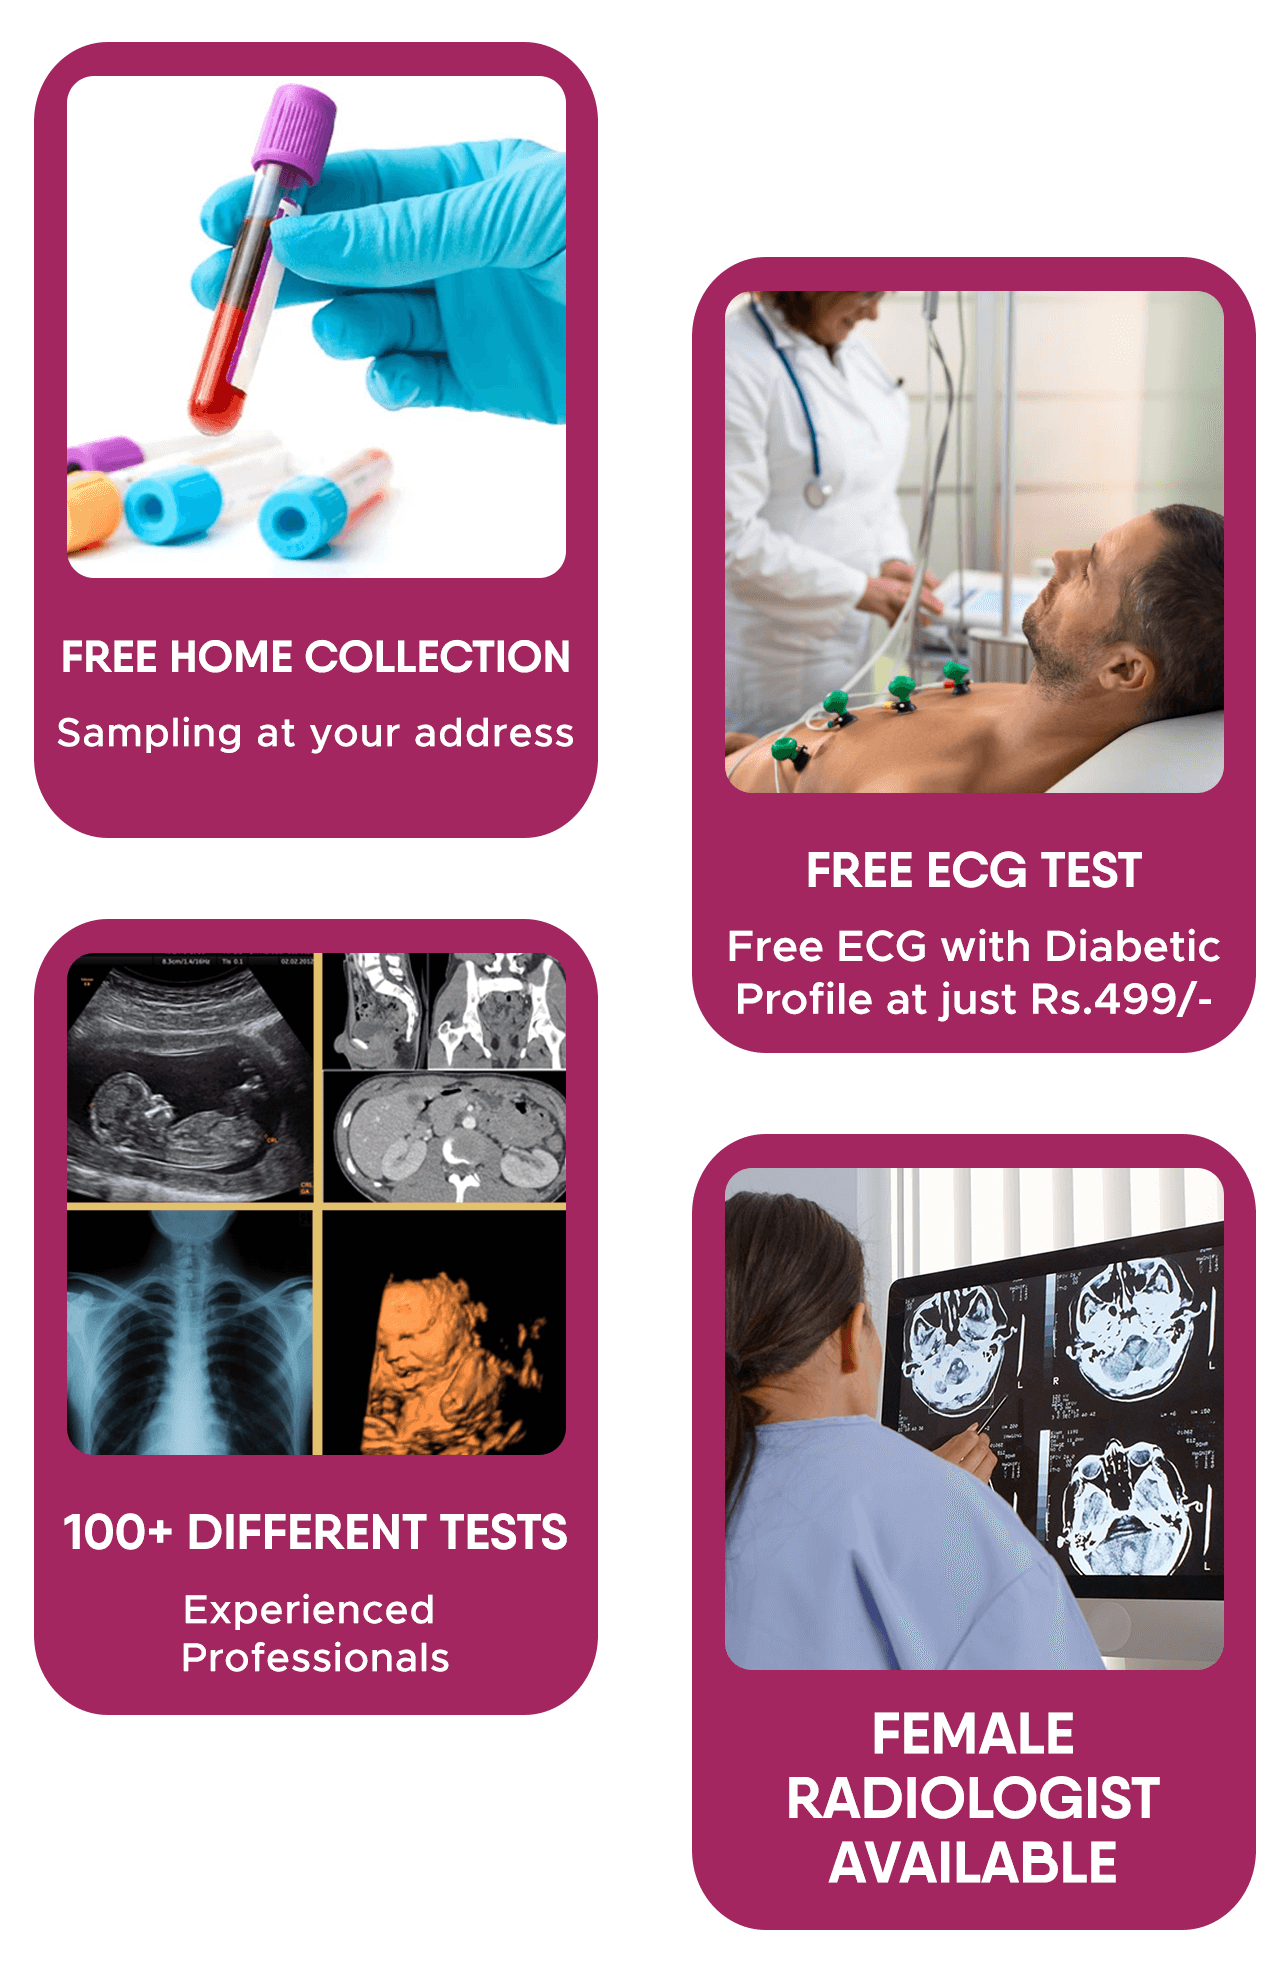

Welcome to AVR Scan

Our doctors are on call 24/7. Same Day Appointments Available.

High-End Technology

State-of-the-art technology We are using at AVR Scan